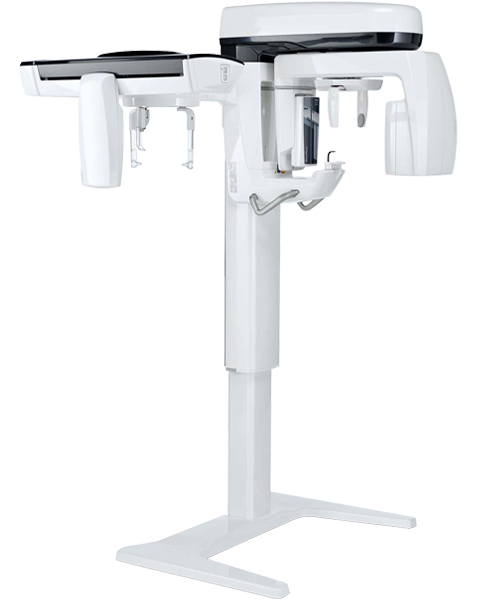

3 конфигурации, отвечающие любым клиническим и диагностическим задачам

Расширенный клинический потенциал отвечает всем требованиям 2D диагностики благодаря модулю CEPH

Компактный и доступный с передвижным датчиком PAN-CEPH, модуль CEPH оснащен специальной опорой для головы с боковыми рычагами в двух вариантах длины. Приложение CEPH можно интегрировать при покупке или установить впоследствии на оборудование, поставляемое в версии CEPH Ready. Все обследования выполняются согласно специальным протоколам для взрослых и детей, снижающим облучение пациента, опираясь на реальные требования к сканированию. Точная оценка перед установкой брекетов, визуализация височно-нижнечелюстного сустава и гайморовых пазух, боковая и фронтальная телерентгенография.